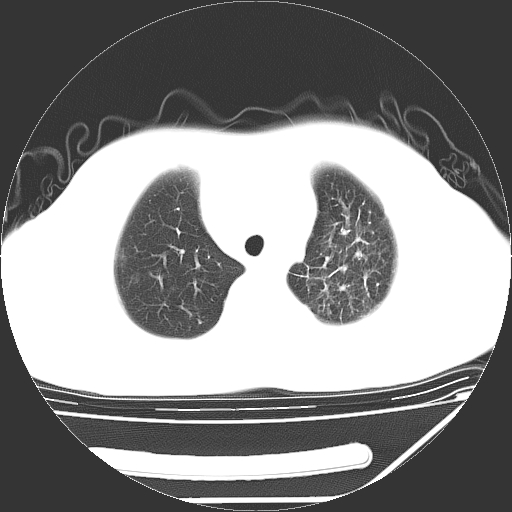

男,13岁,咳嗽、咳痰伴发热一周。

上纵隔课件多枚淋巴结,部分相互融合,左侧支气管壁增厚,肺纹理较右侧增粗,患者,男,13岁,

中上纵隔见多枚淋巴结肿大,部分相互融合成团片,左肺门增大,上叶支气管变窄,肺内多处斑片状 索条状及棉絮状致密影。临床“男,13岁,咳嗽、咳痰伴发热一周。”首先考虑:原发综合征!不除外淋巴瘤可能!

纵隔多发肿大淋巴结,部份有融合改变。双肺血管气管束增厚,以肺门为中心向外周散发,以左肺下叶为明显。考虑淋巴瘤可能性大。不除外原发综合征。

中上纵隔见多枚淋巴结肿大,部分相互融合成团片,左肺门增大,上叶支气管变窄,左肺支气管血管束增粗,可见磨玻璃样影。临床“男,13岁,咳嗽、咳痰伴发热一周。”首先考虑:淋巴瘤可能性大!

中上纵隔见多枚淋巴结肿大,部分相互融合成团片,纵隔内脂肪间隙模糊,左肺门增大,上叶支气管变窄,左肺支气管血管束增粗,可见磨玻璃样影。考虑纵隔淋巴管炎

单纯看片子感觉左侧肺通气不畅,而不像肺内病变引起的纵隔病变。而且纵隔及左肺门都有淋巴结增大。首先还是考虑一下结节病,不排除淋巴瘤!!!